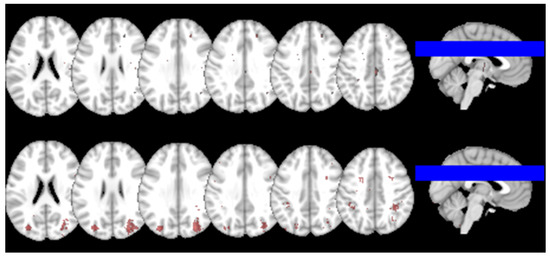

2.5. Association Between Baseline Brain Microbleeds and 1-year Cognition

3.1. Progression Pattern of IDs and BMBs Following a non-Disabling Ischemic Stroke